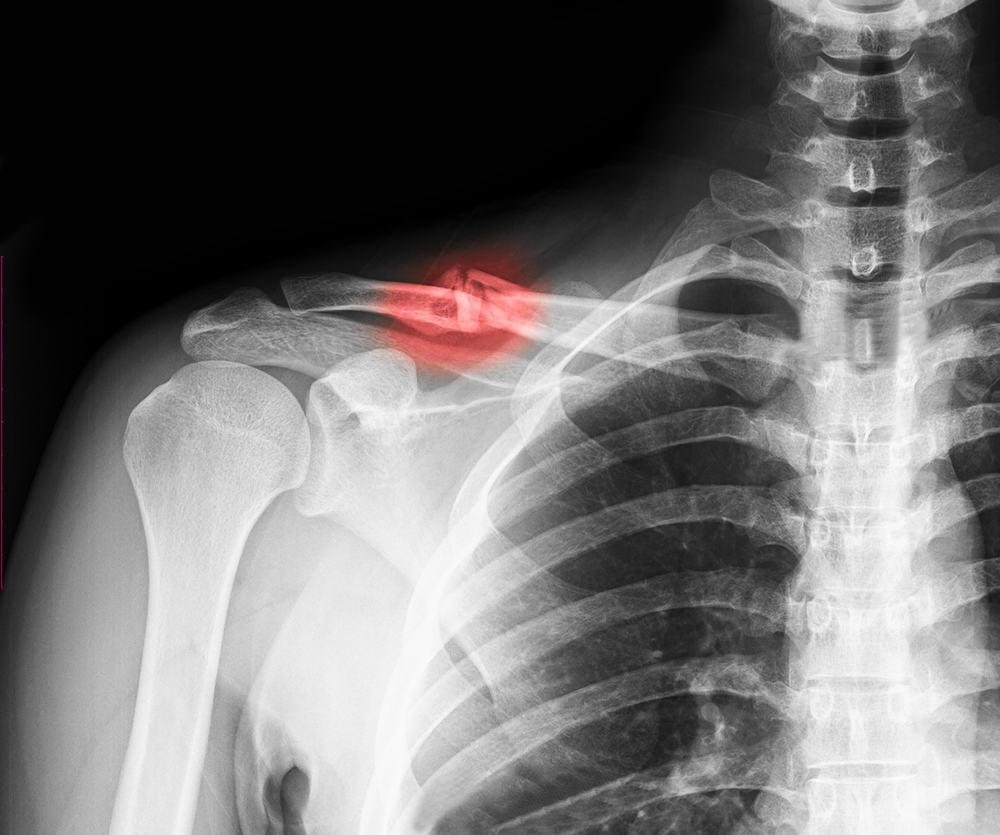

Untuk mendiagnosis fraktur tulang selangka, dokter akan bertanya tentang gejala dan situasi pada saat patah terjadi. Dokter mungkin memeriksa perasaan dan kekuatan di lengan Anda, tangan, dan jari-jari untuk melihat apakah ada kerusakan saraf.

Jika diduga bahwa Anda memiliki patah tulang selangka, dokter akan merekomendasikan sinar-X dari bahu untuk membuat diagnosis lebih lanjut. Sinar-X dapat menampilkan gambar dari patah tulang selangka terkait lokasi dan seberapa parah kondisinya, atau jika ada tulang lainnya yang rusak.

Dalam beberapa kasus, jika dokter perlu melihat fraktur secara lebih detail, computerized tomography (CT) scan akan dilakukan.